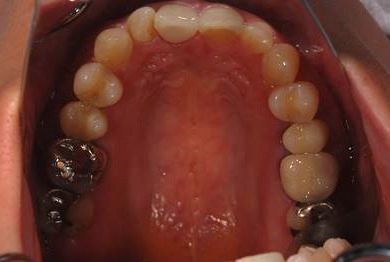

| 性別/年齢 | 女性 / 38歳 | ||||||||||||||||||||||||||||||||

| 主訴 | 右奥歯2本、インレーの相談をしたい。 | ||||||||||||||||||||||||||||||||

| 治療方針 | セラミック治療にて、審美的回復を行う。 | ||||||||||||||||||||||||||||||||

| 治療内容 | ハイブリッドセラミックインレー2本、メタルボンドセラミッククラウン2本(メタルボンド用土台2本)、オールセラミッククラウン1本(オールセラミック用土台1本) | ||||||||||||||||||||||||||||||||